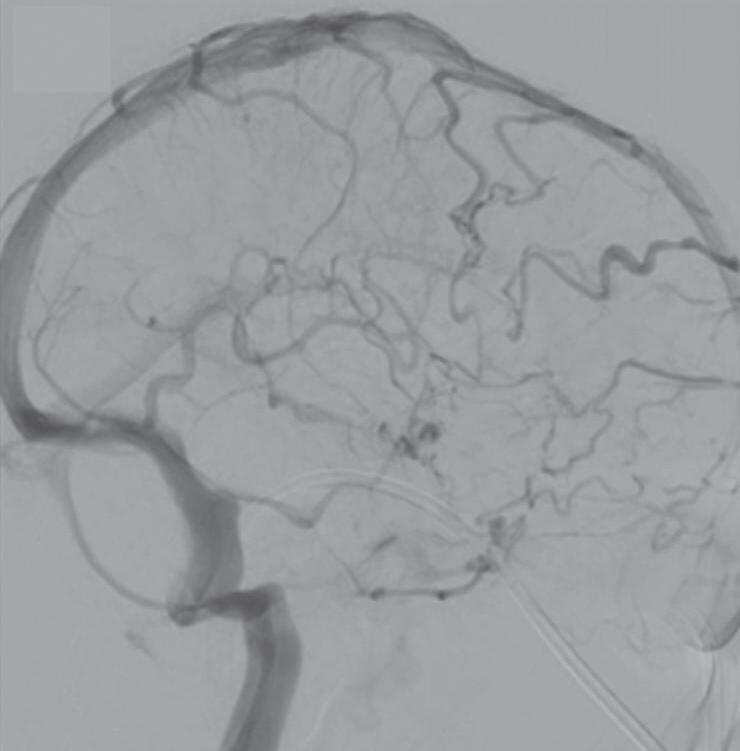

Com relação ao fluxo no interior do nidus, alguns autores classificam-nas em alto fluxo (Fig. 1-8) e baixo fluxo (Fig. 1-9). São consideradas de alto fluxo aquelas em que a opacificação após injeção de contraste ocorre apenas na malformação, em contrapartida, nas de baixo fluxo, ocorre opacificação da MAV e de outras artérias normais do mesmo território vascular. Exemplificando as lesões de alto fluxo temos as malformações arteriais, as malformações arteriovenosas e as fístulas arteriovenosas, enquanto as lesões de baixo fluxo são representadas pelas malformações venosas, linfáticas e capilares.25

Fig. 1-8. (a-c) RNM T1 com contraste, cortes sagital (a), coronal (b) e axial (c) demonstrando MAV não rota com nidus localizado no lobo occipital à esquerda (setas longas). (d) Arteriografia digital cerebral com injeção de contraste via carótida direita (AP) mostrando a contribuição da carótida direita na irrigação da MAV contralateral. (e,f) Com injeção de contraste via carótida esquerda, em Perfil e AP respectivamente, observa-se nidus compacto nutrido por ramos da artéria cerebral média à esquerda e a veia de drenagem precoce se dirigindo para o seio sagital superior. Projeções em AP (g) e em perfil (h) demonstrando a contribuição do sistema vertebrobasilar por meio de ramos distais da artéria cerebral posterior à esquerda e drenagem para os seios sagital superior e sigmoide à esquerda (setas curtas).